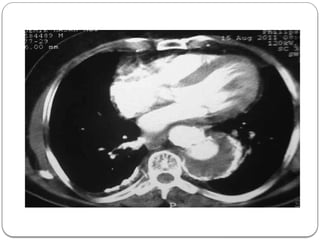

2. Thorax CT scan showed that the mass was located in the proximal part of the

descending aorta, with a diameter of 8 cm, suggesting a saccular aortic aneurysm

3. Defined thrombus material was pressurising the posterior of the oesophagus and the

left atrium. Also, due to compression, atelectasis was seen on the posterobasal

SUPPORTING EXAMINATION: 1. Inechocardiographic examination, systolic function was normal (fractional shortening: 30%, ejection fraction: 65%), there was grade I diastolic dysfunction, mitral lid E-A velocity: 0.7 m/s, no mitral failure, no valvular regurgitation and hypertrophy (interventricular septum diastolic diameter: 10 mm). 2. Thorax CT scan showed that the mass was located in the proximal part of the descending aorta, with a diameter of 8 cm, suggesting a saccular aortic aneurysm 3. Defined thrombus material was pressurising the posterior of the oesophagus and the left atrium. Also, due to compression, atelectasis was seen on the posterobasal segment of the left lung 4. Thoracic aortography examination showed an aneurysm located in the proximal part of the descending aorta with a diameter of 8 cm 5. A large thrombus (6 cm) and atherosclerotic atheroma plaques were shown within theTAA